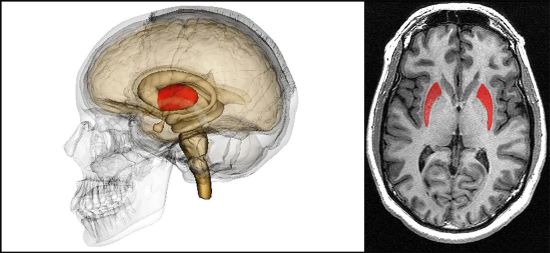

De hecho, dijo que muchos de los sujetos involucrados en contacto directo con los ovnis mostraron habilidades cognitivas sorprendentes, que definió con el término "precognición", posibles gracias al desarrollo de un área particular del cerebro. El inmunólogo de Stanford, el Dr. Garry Nolan también ha realizado investigaciones sobre este tema y, aunque sus conclusiones no son definitivas, existen dos teorías al respecto: la primera, que las personas con un "putamen caudado" naturalmente grande podrían ser como antenas que llaman la atención de los pilotos de la UAP. La segunda, que los encuentros de los UAP con personas pueden provocar que esa parte del cerebro aumente de tamaño.

"Esta es una parte del cerebro conocida como putamen caudado, y es una parte muy específica del cerebro responsable de todo tipo de cosas; algunos incluso han especulado sobre la precognición".

Elizondo afirmó, por tanto, que esta parte del cerebro es más grande en personas con poderes psíquicos particulares, o lo que, según dijo, el gobierno estadounidense llama "visión remota". Que se trata de una verdad histórica, es decir, que el gobierno americano, en este caso la CIA, estaba interesado en estos poderes de la psique lo demuestra, por ejemplo, el documento desclasificado descargable en este enlace: https://www. cia.gov /readingroom/docs/CIA-RDP96-00791R000200180005-5.pdf

De hecho, argumentó que las personas con putamen caudado mejorado podrían tener talento tanto para la visión remota como para la comunicación con los UAP, subrayando el gran interés mostrado por el Pentágono en estas facultades con fines militares.

"Muchas personas que participaron en el programa de visualización remota se han sometido a resonancias magnéticas del cerebro y la gran mayoría tiene esa morfología específica", dijo Elizondo. Según él, él mismo había sido entrenado para obtener estas facultades cognitivas y conocía su funcionamiento real, por lo que comenzó a experimentar lo que en el ambiente de la UAP se conoce como el "efecto autoestopista", una fenomenología en la que Objetos Voladores No Identificados comienzan a aparecer en las casas de estos sujetos, probablemente atraídos por esta habilidad: una experiencia que el propio Elizondo vivió en primera persona: "Teníamos estas extrañas esferas de luz incandescente en la casa", dijo. "Eran verdes, pequeñas, difusas, un poco como pequeñas esferas de neón".